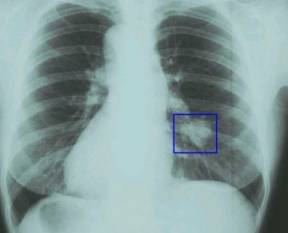

“Рак легких с метастазами” – сколько живут при таком поражении зависит от локализации, вида и распространения опухоли. Начальные стадии метастатического поражения протекают бессимптомно, что объясняет позднюю диагностику заболевания. Дальнейшее развитие болезни формирует яркую клиническую картину с болевым синдромом и раковой интоксикацией. Медицинская помощь таким онкобольным базируется на симптоматическом лечении отдельных признаков заболевания. Прогноз 4 стадии рака легких неблагоприятный с максимальной длительностью жизни до 18 месяцев.

Рак легких с метастазами – сколько живут? Прогноз

Рак легких с метастазами – сколько живут пациенты обуславливает локализация вторичной опухоли. Наименее благоприятный прогноз для метастазов в печеночную ткань (4-6месяцев). Злокачественные очаги в костной ткани, по статистике, дают возможность онкобольным прожить до 12 месяцев. Продлить жизнь больному может только своевременная и адекватная противораковая терапия.